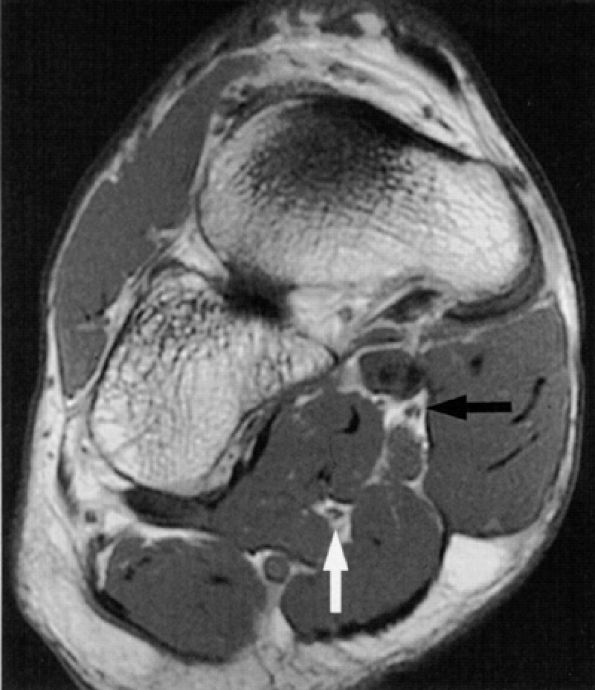

Muscle denervation edema or atrophy of the abductor hallucis and flexor digitorum brevis muscles, seen on MR images of the ankle, is compatible with medial plantar nerve entrapment (Fig. 6.52).

-

Denervation of the first lumbrical and of the flexor hallucis brevis muscle, also consistent with medial plantar nerve entrapment, is better seen on MR images of the foot (Figs. 6.53 and 6.54).

Abductor hallucis muscle hypertrophy and plantar fasciitis with medial calcaneal spur formation and adjacent soft-tissue edema are suggestive of entrapment of the first branch of the lateral plantar nerve.

In our experience, incidental MR detection of denervation edema and atrophy of the abductor digiti quinti muscle is not uncommon and most likely reflects a clinically missed entrapment of the first branch of the lateral plantar nerve (Figs. 6.55 and 6.56).